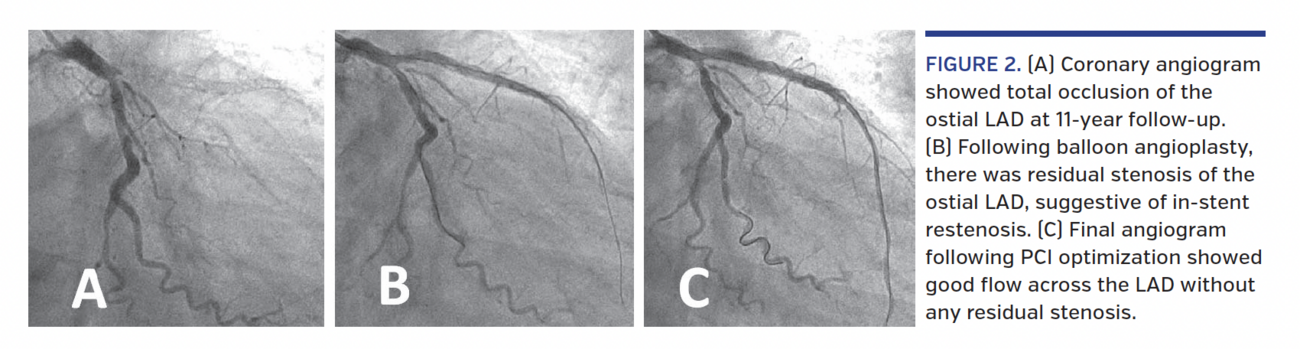

54-year-old, non-diabetic, normotensive, non-smoker male presented with acute anterior-wall myocardial infarction (AWMI) at the emergency room in August 2007. He underwent primary angioplasty of an occluded proximal left anterior descending (LAD) (Figure 1A), and two overlapping 2.75 x 23 mm and 2.5 x 33 mm Cypher stents (Cordis Corporation) were deployed from ostial to distal LAD (Figure 1B). Intravascular imaging was not performed during the percutaneous coronary intervention (PCI). A follow-up angiogram after 4 years showed patent LAD stents (Figure 1C). In August 2018 (11 years after PCI), he again presented with acute AWMI despite continued dual-antiplatelet therapy. Coronary angiography revealed total occlusion of the proximal LAD (Figure 2A). The lesion was crossed with a Choice PT coronary guidewire (Boston Scientific) and sequentially dilated with 1.25 x 15 mm and 2.5 x 15 mm balloons (Figure 2B). Intravascular ultrasound revealed mild neointimal hyperplasia in the proximal-mid LAD and a markedly under-expanded and malapposed stent throughout its length from ostial to distal LAD (Figure 3; Video 1). The mean luminal diameter (MLD) and mean vessel diameter (MVD) of the proximal LAD (2.31 mm vs 4.14 mm) and distal LAD (2.10 mm vs 3.55 mm) showed a gross mismatch suggestive of malapposition (Figure 3). The entire stented segment was dilated with a 3.5 x 15 mm non-compliant balloon and the ostial-proximal LAD was additionally dilated with a 4 x 12 mm non-compliant balloon. TIMI-3 flow was achieved in the LAD (Figure 2C). Repeat IVUS revealed well-apposed stent struts, with mean cross-sectional area of 9.50 mm2 and MLD of 3.65 mm in the proximal LAD and cross-sectional area of 7.02 mm2 and MLD of 3.10 mm in the distal LAD (Figure 4; Video 2). As the result was optimal, no additional stent was deployed across the LAD. Patient was discharged on dual-antiplatelet therapy and was asymptomatic at 3-month follow-up exam.